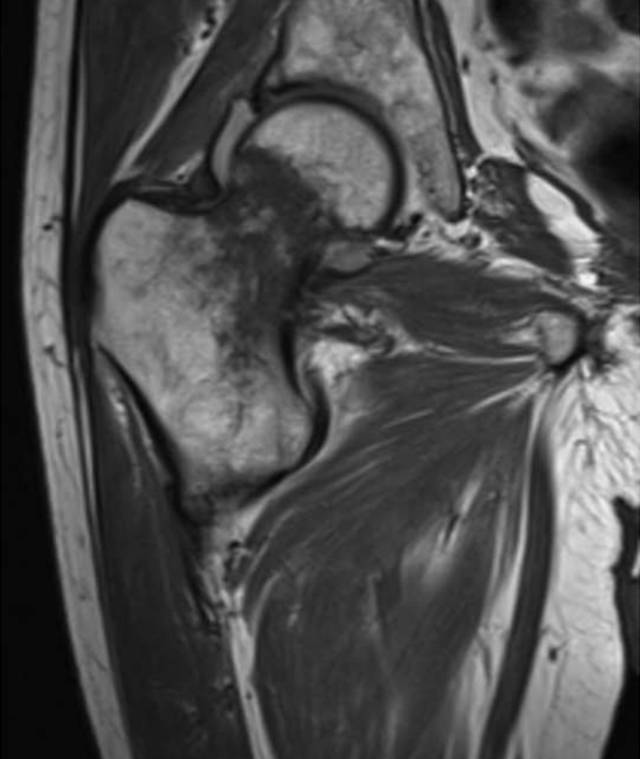

即使正确定位和技术上优秀的射线照片,一些骨折在X线片上是不可检测的,因为它们是无位移的。这些骨折有症状,并有相应的临床表现和受伤的机制,但他们没有明显的X光片。在本质上,X射线照片结果是假阴性的,因为该方法本身局限性不足以显示断裂。 射线照片上的急性骨折的检测通常需要它们在一定程度上移位。由于临床体征高度怀疑,通常需要进一步评估额外的成像,特别是如果这种成像的结果将影响临床管理。这样的例子有上了年纪的人或老年人在地面踉跄之后加上不能承受体重,髋部疼痛, 骨质疏松通常进一步增加了检测不位移性骨折的难度。放射线检查结果可能是阴性或模棱两可的,因为骨矿物的弥漫性损失使不位移性骨折线不太明显。因为近端股骨骨折的管理通常是手术,当根据临床表现的骨折的预测概率高时,通常进行进一步的CT或MRI评估。美国放射学会[12]建议对中年或老年患者进行MRI(等级9)CT(等级6)或放射性核素骨扫描(等级4),这些患者在放射照片显示阴性或不确定性,用CT与MRI的诊断优势以排除存在放射学上隐匿性髋骨骨折[13]。如果MRI不可用或者患者对MRI具有禁忌症,CT可以提供最佳选择。然而,MRI在检测骨髓水肿方面优越(图3)。骨扫描已应用于放射摄影术的初步诊断[14],但在我们的实践中最少使用,因为CT更为普遍。床旁超声检查最近被研究作为一种检测第五跖骨骨折的方法,基本上作为身体检查的延伸,并且与放射线照片相比显示出一些前景[15]。然而,在多发伤筛查情况下,超声检查的成像效果不如放射照相[16]。

图3B-65岁的男子在地面摔倒后,在射线照片上没有看到移位性骨折。冠状T1加权MRI显示无错位股骨颈骨折。